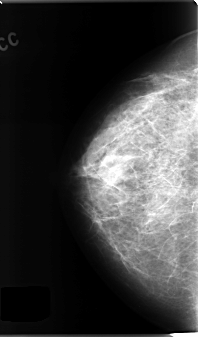

C_0136_1.LEFT_CC

LEFT_CC LINES 4816 PIXELS_PER_LINE 2712 BITS_PER_PIXEL 12 RESOLUTION 50 NON_OVERLAY